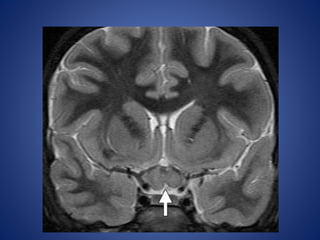

• #16 Optic pathway astrocytoma in an 8-year-old child with NF-1. (a) Coronal T2WI shows enlargement of the optic chiasm (arrow), which is hyperintense relative to white matter.

• #17 Sagittal T1WI shows the isointense enlarged optic chiasm (arrow).